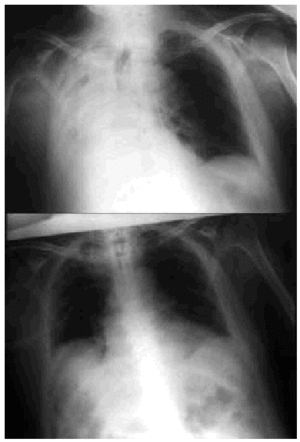

Fig. 5. Right-sided atelectasia in a patient with very advanced Alzheimer's disease who was unable to achieve an effective cough. After 6 hours of mechanical insufflation-exsufflation therapy and oronasal mask (every 15-30 minutes), and without any self-assistance, the atelectasia disappeared.